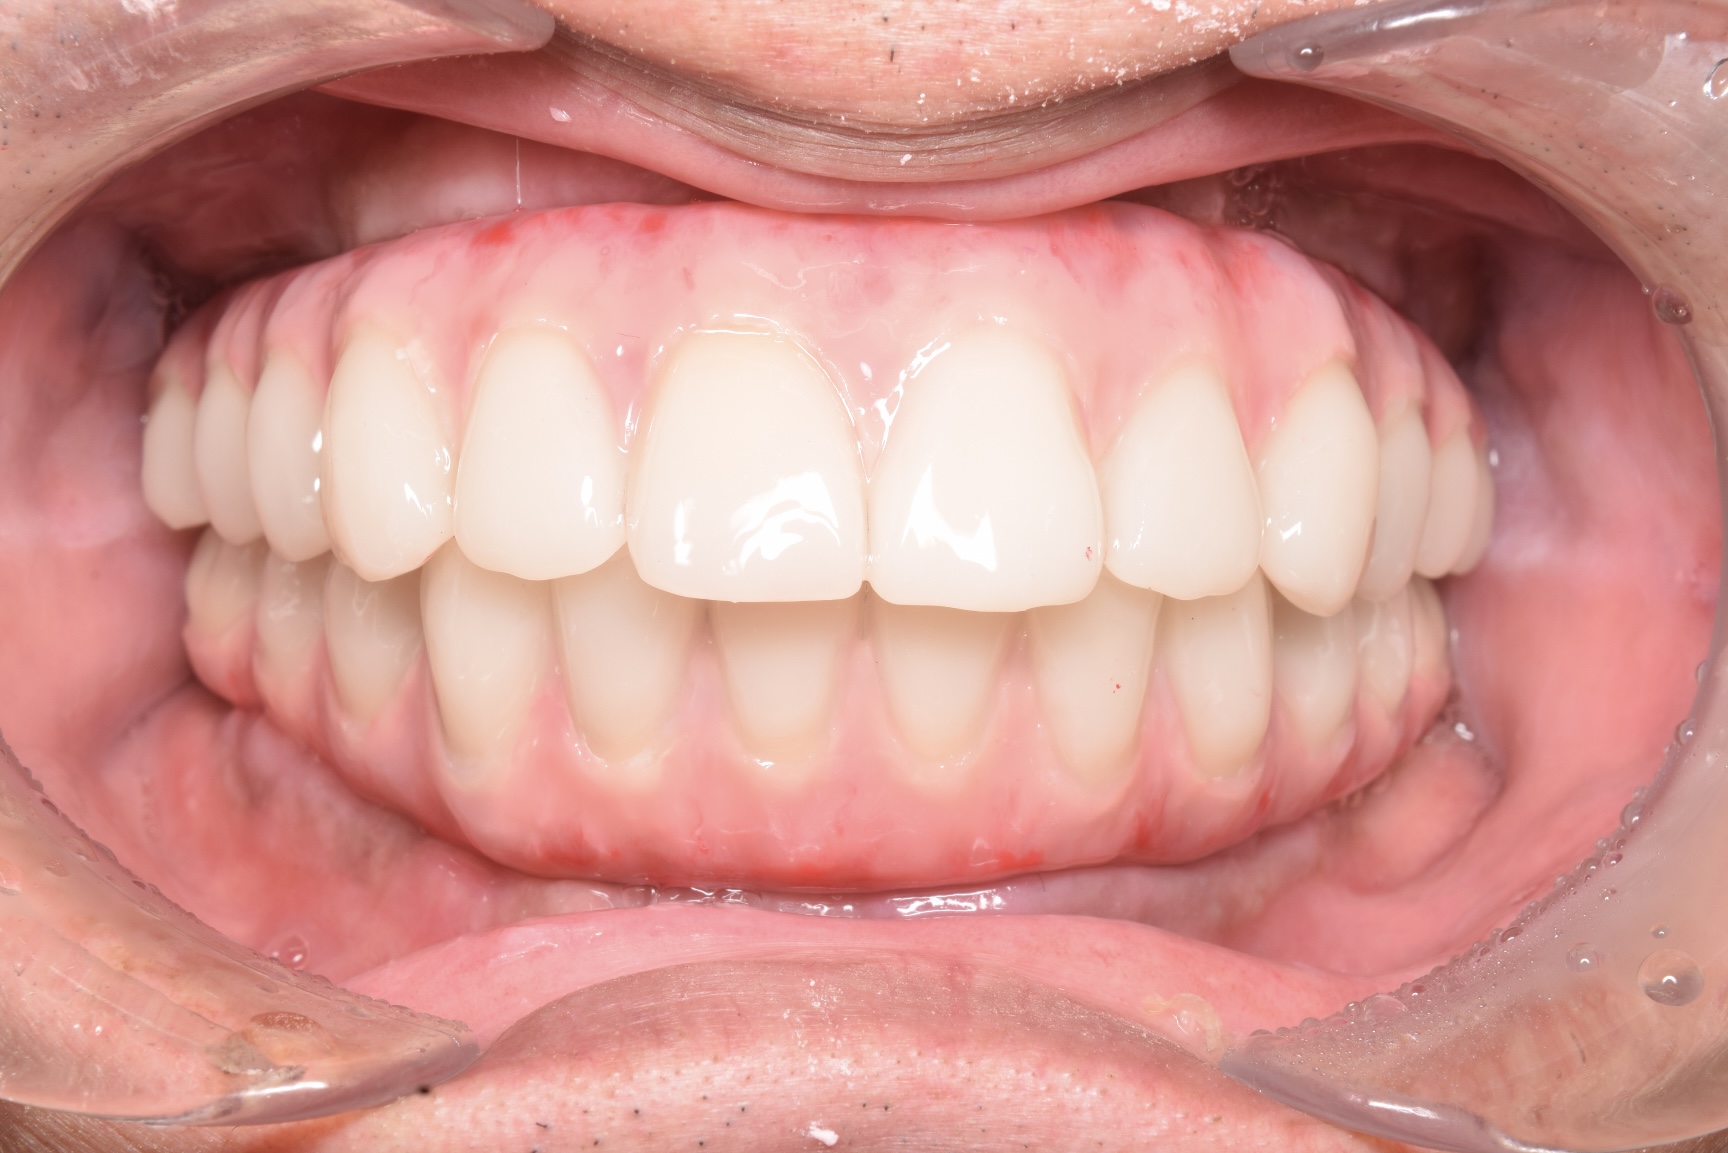

治療を終えて